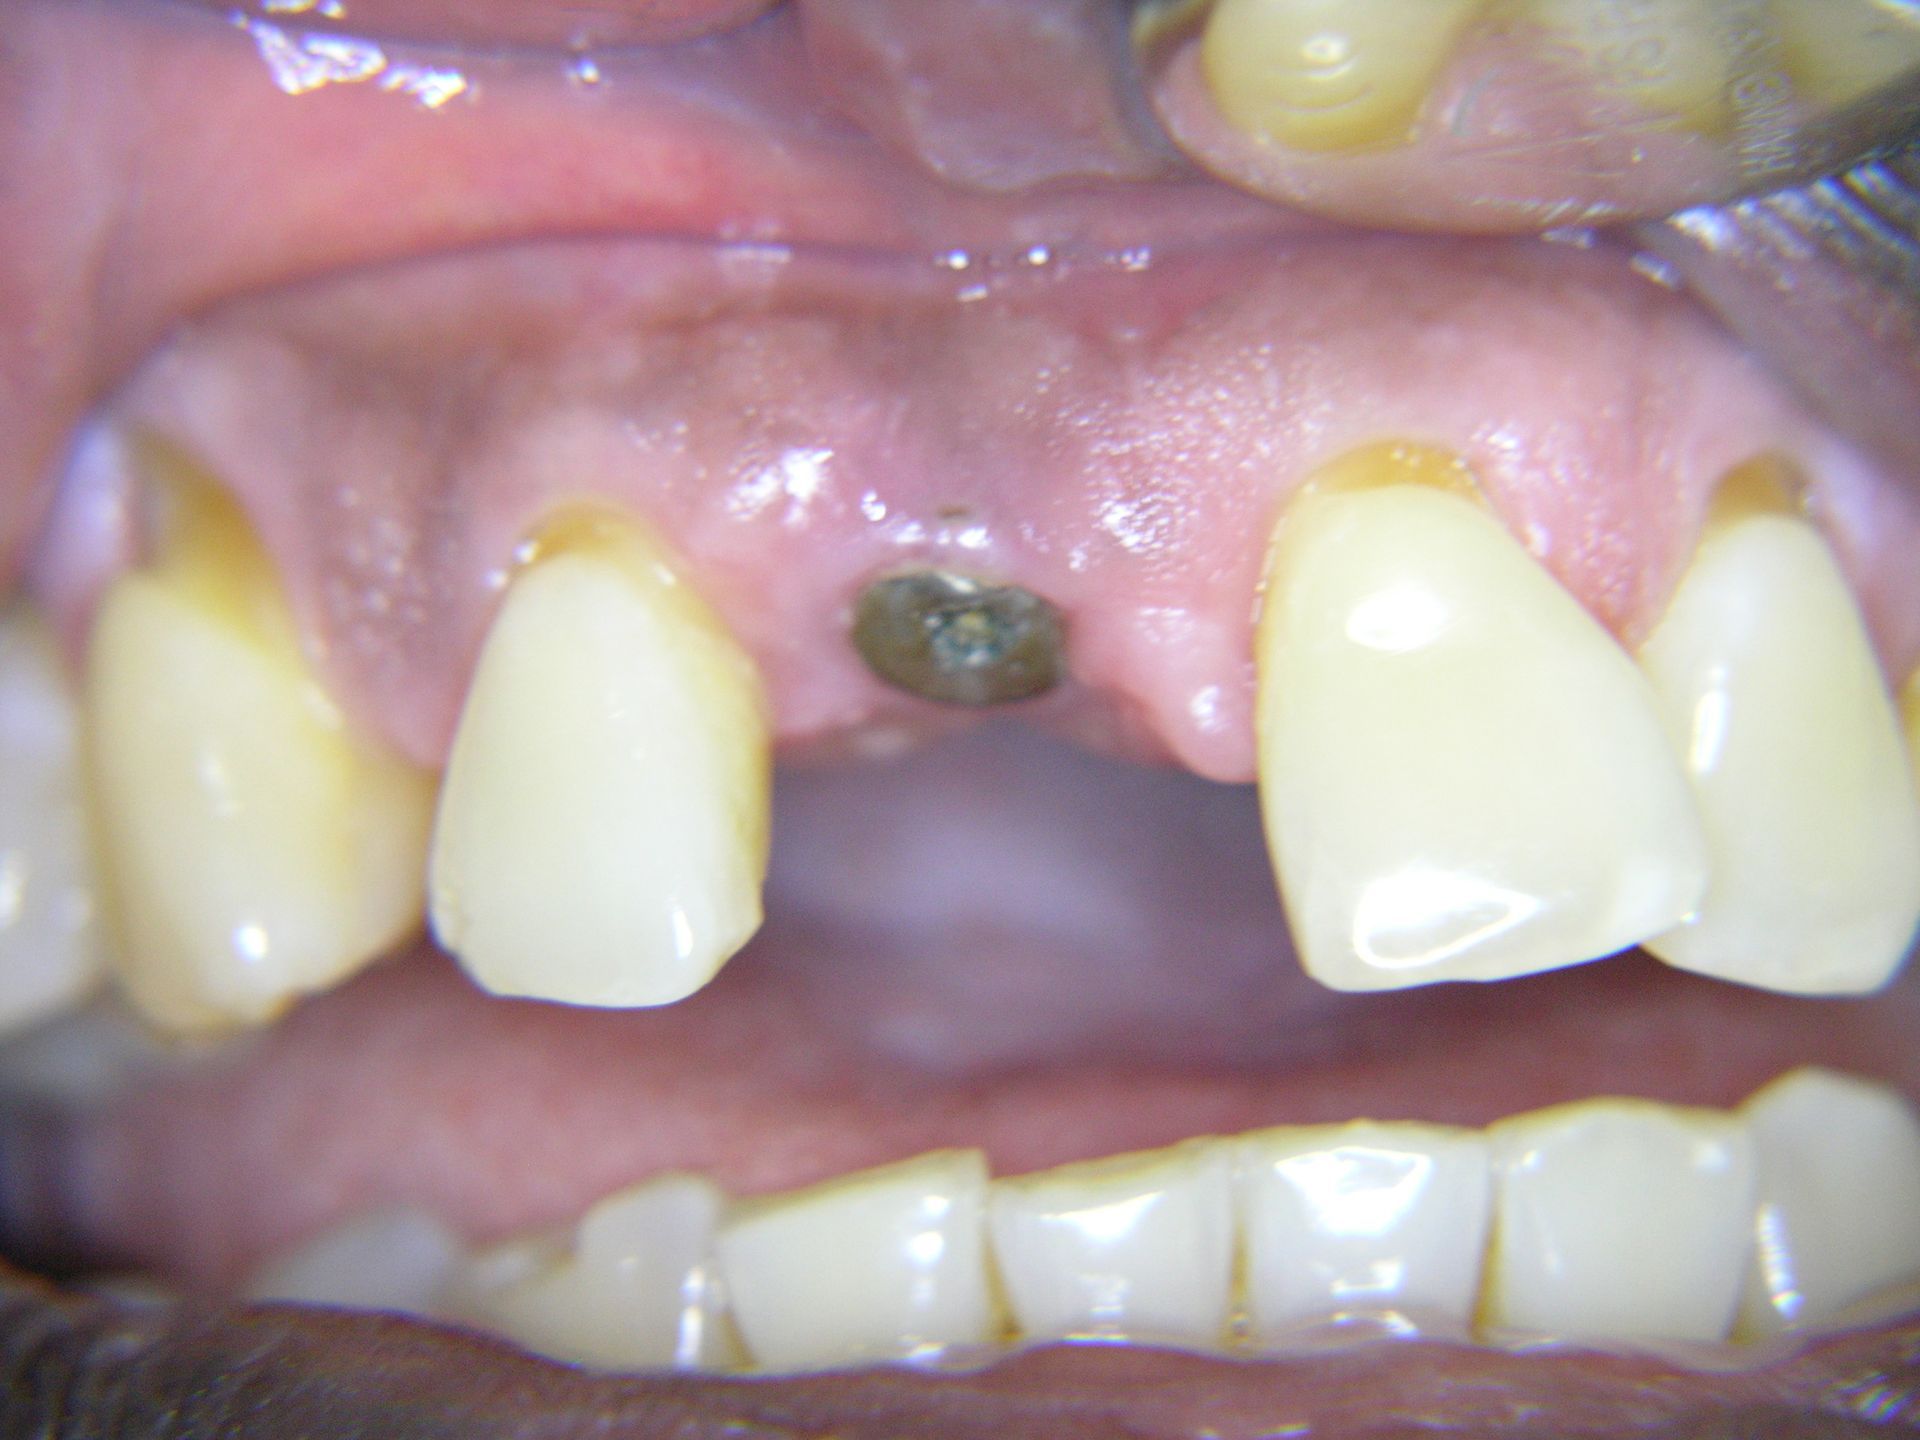

Beispiele von Versorgungen